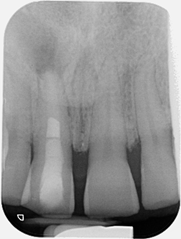

Multi-disciplinary: root canal treatment, molar apicectomy and bone regeneration

Pre-operative X-ray